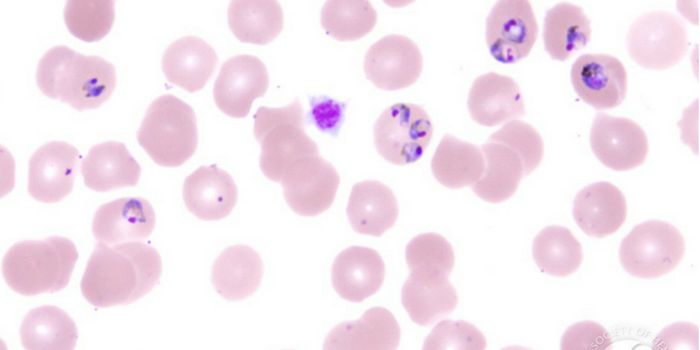

MAY 21, 2018CancerThe malarial parasite expresses a protein, VAR2CSA, that binds to chondroitin sulfate (CS) found on both placental and c ...